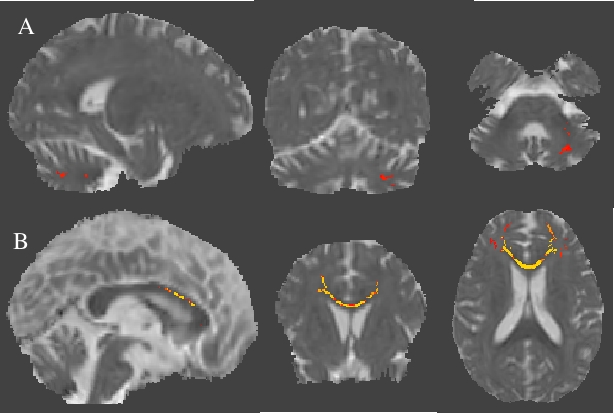

Figure1: Fractional anisotropy (FA) maps overlaid on mean FA skeleton using Tract-Based Spatial Statistics derived statistics (p<0.05) of Diffusion tensor imaging (DTI) data in (A) SCA1 in comparison with controls, (B) SCA2 in comparison with controls, (C) SCA12 in comparison with controls, (D) SCA2 in comparison with SCA12 and (E) SCA1 in comparison SCA12.

Figure2: Radial diffusivity (RD) maps overlaid on mean RD using Tract-Based Spatial Statistics derived statistics (p<0.05) of Diffusion tensor imaging (DTI) in (A) SCA2 in comparison with SCA1, (B) SCA12 in comparison with SCA1.

Figure3: Axial diffusivity (AD) maps overlaid on mean AD using Tract-Based Spatial Statistics derived statistics (p<0.05) of Diffusion tensor imaging (DTI) in (A) SCA2 in comparison with SCA12 and (B) SCA1 in comparison with SCA12.